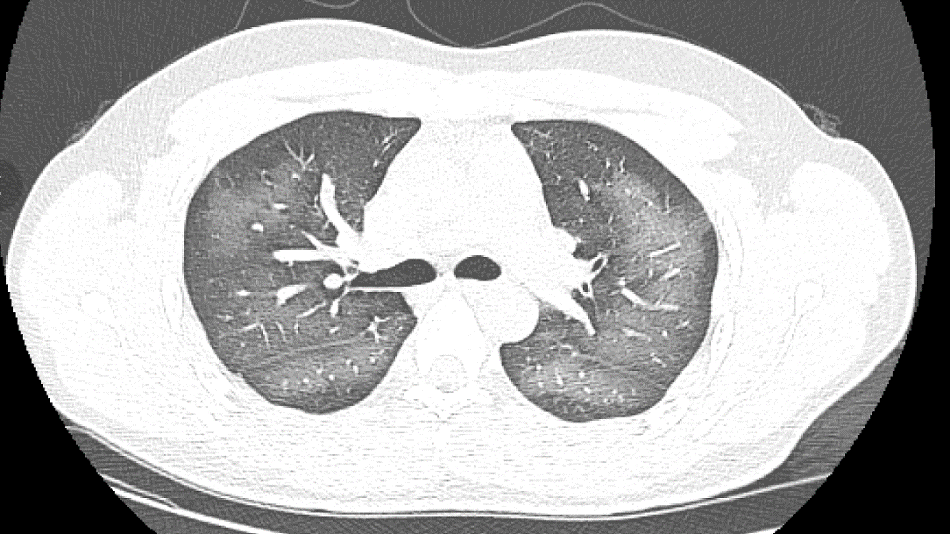

卻在使用后會出現“白肺”

原來,小伙李林(化名)外出前使用了防曬噴霧,在對著面部噴灑時一不小心誤吸,隨即出現胸悶、咳嗽的癥狀。癥狀一直持續到第二天仍未好轉。經檢查,因吸入噴霧,導致李林雙肺赫然呈現大范圍白色樣病變,報告提示“白肺”。關于噴霧式防曬霜